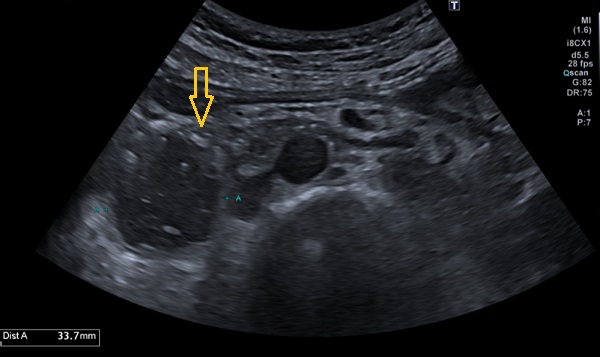

En el estudio analítico se objetivó alcalosis metabólica (pH 7,53, HCO3 33,8, EB +11,2), leucocitosis con neutrofilia y elevación leve de transaminasas. Se realizó estudio de imagen mediante ecografía abdominal, con hallazgo de dilatación de la segunda porción duodenal y colapso de la tercera porción por una pinza aortomesentérica (Figura 1).

| Figura 1. En esta ecografía abdominal se visualiza la notable dilatación de la segunda porción duodenal, durante la fase clínica del paciente |